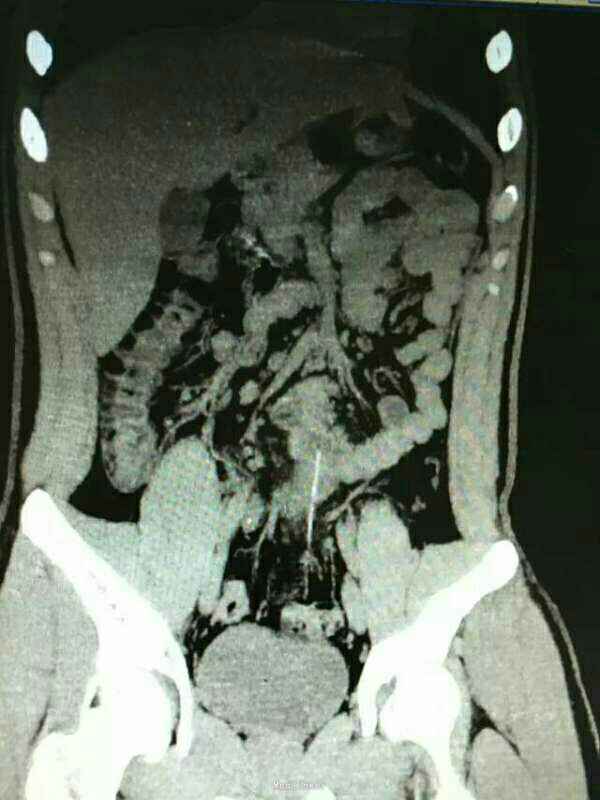

患者,男,16岁,酒后吞食异物后出现疼痛2小时急诊入院

查体:腹部疼痛不适,无明显腹膜刺激征 辅助检查:腹部彩超未见明显异常,胸片可见右肾区异物,CT如图所示

诊断:回肠异物合并贯通伤 治疗:急诊手术异物取出,如图所示。